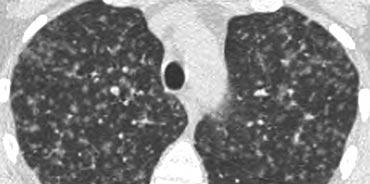

Mosaic attenuation

Thuật ngữ suy giảm khảm mô tả sự khác biệt về tỷ trọng giữa các vùng phổi bị tổn thương và không bị tổn thương, tạo ra hình ảnh loang lổ xen kẽ giữa các vùng phổi sáng và tối. Vai trò của bác sĩ X-quang là xác định thành phần nào — vùng phổi tối hay vùng phổi sáng — là bất thường.

Khi đục kính mờ (GGO) biểu hiện dưới dạng suy giảm khảm, hãy xem xét các khả năng sau:

- Infiltrative processes adjacent to normal lung.

- Phổi bình thường có hình ảnh tương đối đậm hơn so với các vùng phổi có bẫy khí.

- Phổi tăng tưới máu liền kề với phổi giảm tưới máu do bệnh huyết khối tắc mạch mạn tính.

Việc phân biệt các thực thể này có thể là một thách thức. Hai dấu hiệu chẩn đoán giúp phân biệt thêm:

- Expiratory scans for air trapping.

- Đánh giá mạch máu:

- Nếu mạch máu kém rõ hơn ở vùng phổi “đen” so với phổi “trắng”, thì vùng phổi “đen” có khả năng là bất thường. Điều này gợi ý viêm tiểu phế quản tắc nghẽn hoặc thuyên tắc phổi mạn tính. Chụp cắt lớp thì thở ra có thể giúp phân biệt các tình trạng này.

- Nếu mạch máu xuất hiện tương tự nhau ở cả vùng phổi “đen” và “trắng”, bệnh nhân có khả năng mắc bệnh phổi thâm nhiễm, chẳng hạn như xuất huyết phổi (như được minh họa ở bên phải).

Suy giảm hệ số hấp thụ dạng khảm trong Viêm phổi quá mẫn

Hình ảnh bên trái cho thấy bệnh nhân có hình ảnh kính mờ phân bố dạng khảm. Một số tiểu thùy bị tổn thương, trong khi các tiểu thùy khác không bị ảnh hưởng.

Chẩn đoán phân biệt bao gồm viêm phổi quá mẫn (HP), viêm tiểu phế quản hoặc bệnh huyết khối tắc mạch.

Tiền sử lâm sàng điển hình của viêm phổi quá mẫn.

HP thường biểu hiện với các nốt trung tiểu thùy có tỷ trọng kính mờ (nốt acinar).

Khi hợp lưu, HRCT cho thấy hình ảnh kính mờ lan tỏa.

HP là bệnh phổi dị ứng do hít phải các kháng nguyên có trong nhiều loại bụi hữu cơ.

Phổi nông dân, hội chứng HP được biết đến nhiều nhất, xảy ra do hít phải các vi nấm trong cỏ khô ẩm hoặc tiếp xúc với chim cảnh.

HP typically manifests in two forms:

- Mờ kính mờ phân bố dạng khảm (như trong trường hợp này).

- Các nốt centrilobular có mật độ kính mờ (nốt acinar).

Suy Giảm Thông Khí Dạng Khảm trong Bệnh Huyết Khối Tắc Mạch Mãn Tính

Hình ảnh bên trái mô tả một bệnh nhân có dạng kính mờ phân bố theo kiểu khảm.

Dấu hiệu chính ở đây là sự giãn rộng của các động mạch phổi (mũi tên) tại các vùng có độ mờ dạng kính mờ.

Hình ảnh này là kết quả của vùng phổi được tưới máu quá mức nằm kề cạnh vùng phổi thiểu máu với khẩu kính mạch máu giảm do bệnh huyết khối tắc mạch mãn tính.

Một bệnh nhân khác (bên trái) cho thấy hình ảnh kính mờ tương tự theo phân bố khảm.

Hình ảnh kính mờ là do vùng phổi được tưới máu nhiều với các mạch máu lớn liền kề với vùng phổi thiểu huyết (mũi tên vàng) với các mạch máu nhỏ do bệnh huyết khối tắc mạch mạn tính.

Huyết khối thành mạch và vách ngăn nội mạch là những đặc điểm điển hình của huyết khối tắc mạch mạn tính, phản ánh sự tái thông một phần (mũi tên xanh).